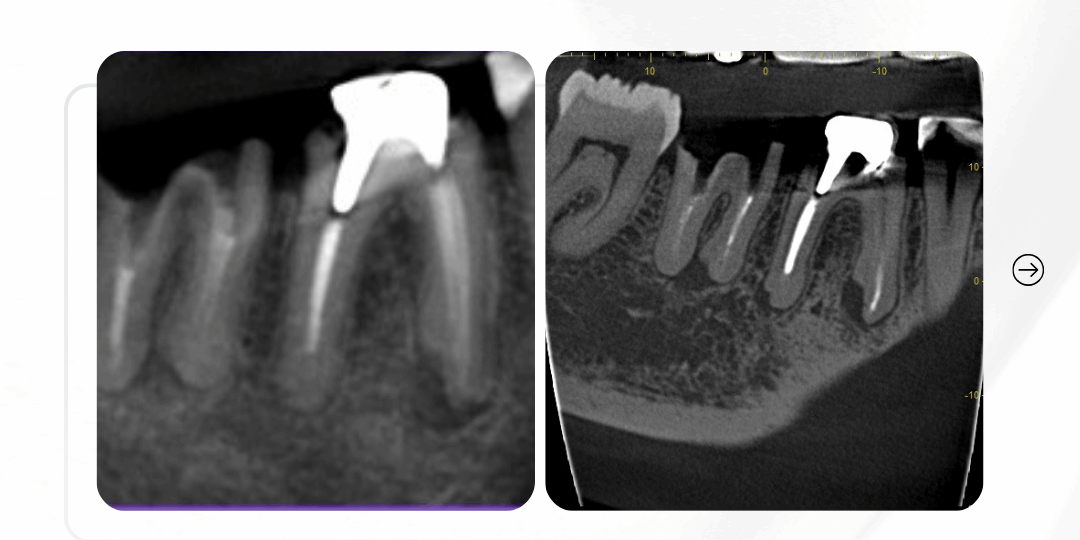

Radiografia inicial

Em síntese, o exame 2D mostra uma imagem aparentemente compatível com falha de tratamento.

Mas… o que exatamente precisa ser retratado?

A imagem levanta a suspeita — mas não responde com precisão.

Comparativo: o que o 2D não mostrou

Na radiografia: indefinição.

Na tomografia: diagnóstico.

– E é com diagnóstico que se conduz retratamento — não com tentativa.